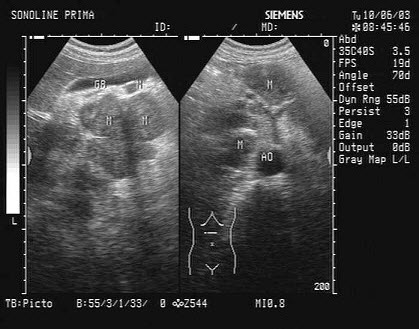

某患者肝门及腹腔可见多个肿块回声。根据声像图表现,最可能的诊断是()

A.肝癌

B.胰腺癌

C.肠系膜肿瘤

D.肿大淋巴结

E.以上都不是